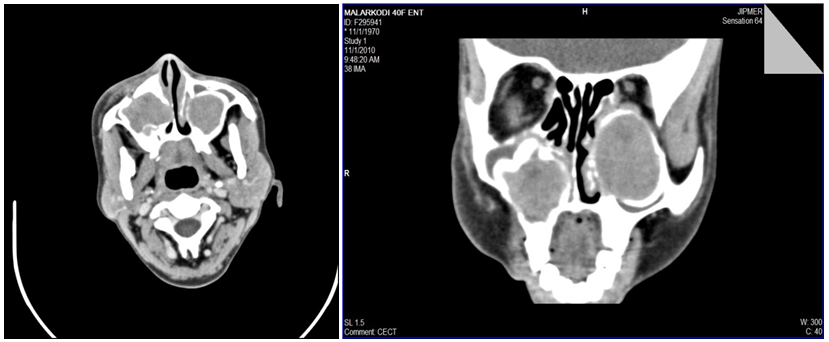

A computed tomography scan of the paranasal sinuses demonstrated an expansile multiloculated osteolytic lesion with soft tissue density within, involving both the maxillae (Figure 2). With the diagnosis of a metabolic disease, laboratory investigations revealed a high serum calcium (12.9 mg /dl ) and a low phosphate level (2.1mg/dl), a raised 24 hour urine calcium of 411 mg/day and a markedly raised urine calcium/creatinine ratio of 0.65 (normal <0.2)and a normal 25(OH))VIT D levels.

Figure 2 Axial and coronal section of computed tomography of bilateral maxillary tumors. It demonstrates expansile multiloculated osteolytic lesion with soft tissue density within, involving both the maxillae.